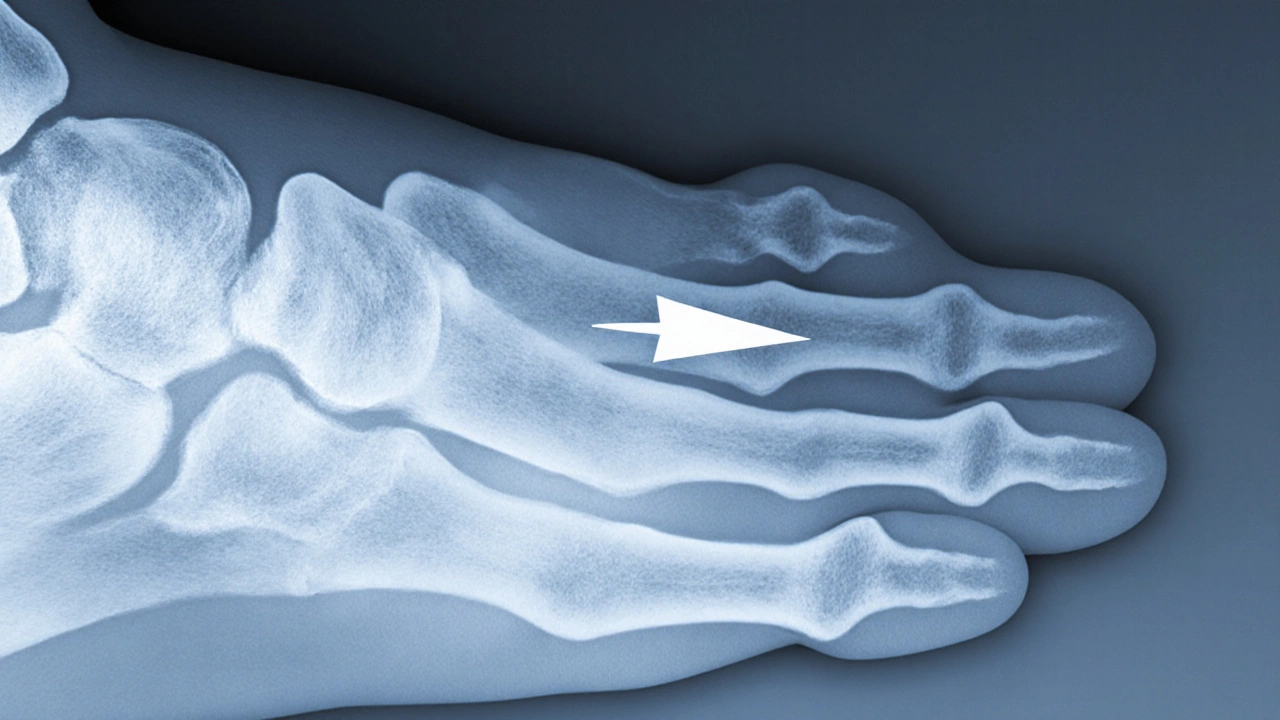

Nejde o něco, co byste mohli vidět nebo dotknout - ostruha je uvnitř těla. Pokud byste měli rentgenový snímek pata, uviděli byste na spodní straně patní kosti malý, ostrý výběžek kosti, který vypadá jako hrot nebo šipka směřující dopředu. V některých případech je vidět i jako malý „hrot“ nebo „zub“ na okraji kosti. Na rentgenovém snímku to vypadá jako jemná, bílá čára, která se od kosti vynořuje směrem k prstům.

Nikdy nevidíte ostruhu zvenčí. Nejde o kámen, ne o vyrážku, ne o něco, co byste mohli pohmatat při masáži. Pokud někdo říká, že „má ostruhu na patě, kterou cítí“, pravděpodobně má zánět fascie, ne ostruhu. Ostruha je vidět jen na snímku, bolest je v tkáni.